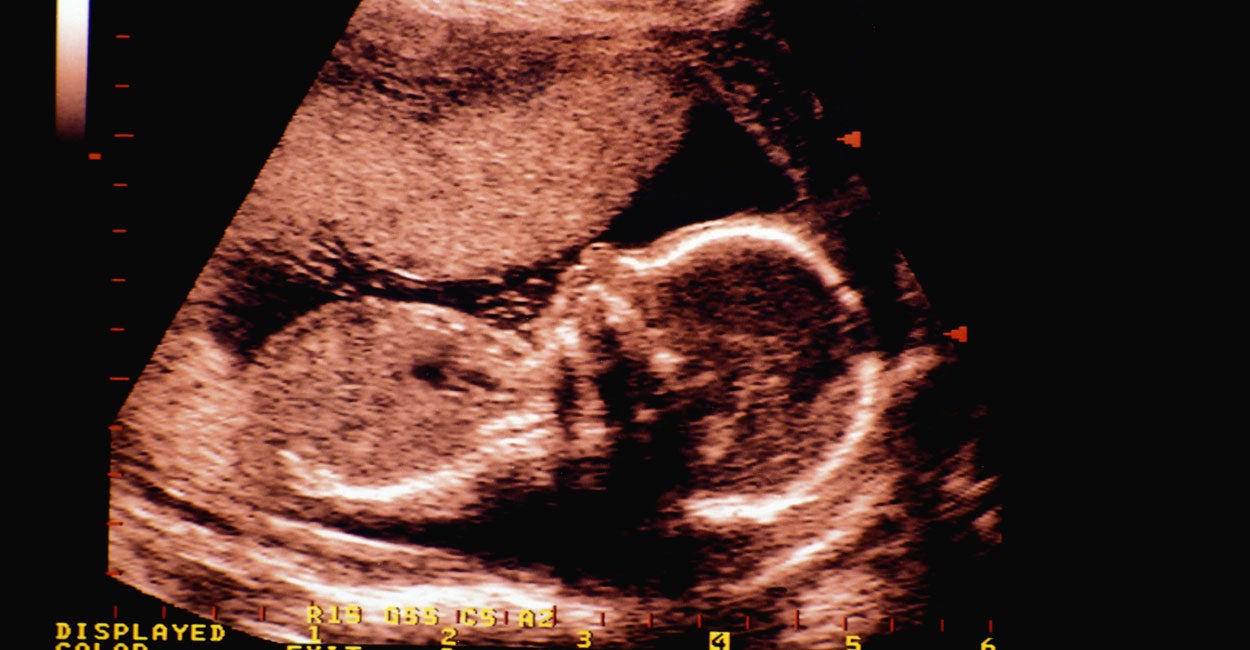

A plaintiff in the case that preceded the ruling included abortion provider Hope Medical Group for Women. The abortion facility offers abortion services up to 16 weeks in pregnancy. The Louisiana Department of Health and Hospitals’ secretary was the defendant in the case, Reuters reported.